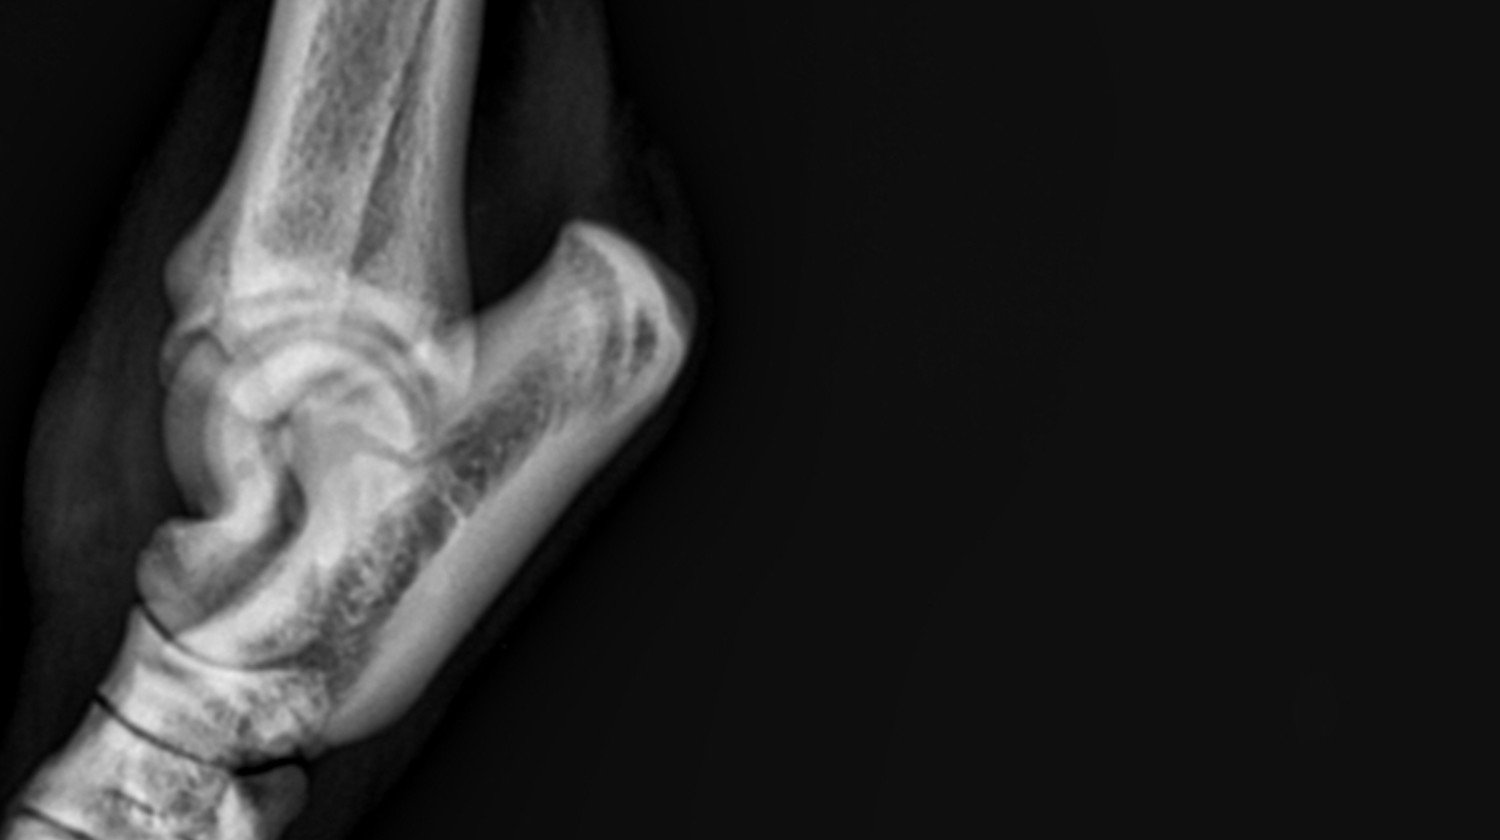

Biegając i bawiąc się po podwórku niefortunnie skoczyłem na tylną łapkę, przez co mam zerwane więzadła!

Bary potrzebuje pilnej operacji, a w późniejszym czasie rehabilitacji, które są bardzo kosztowne.